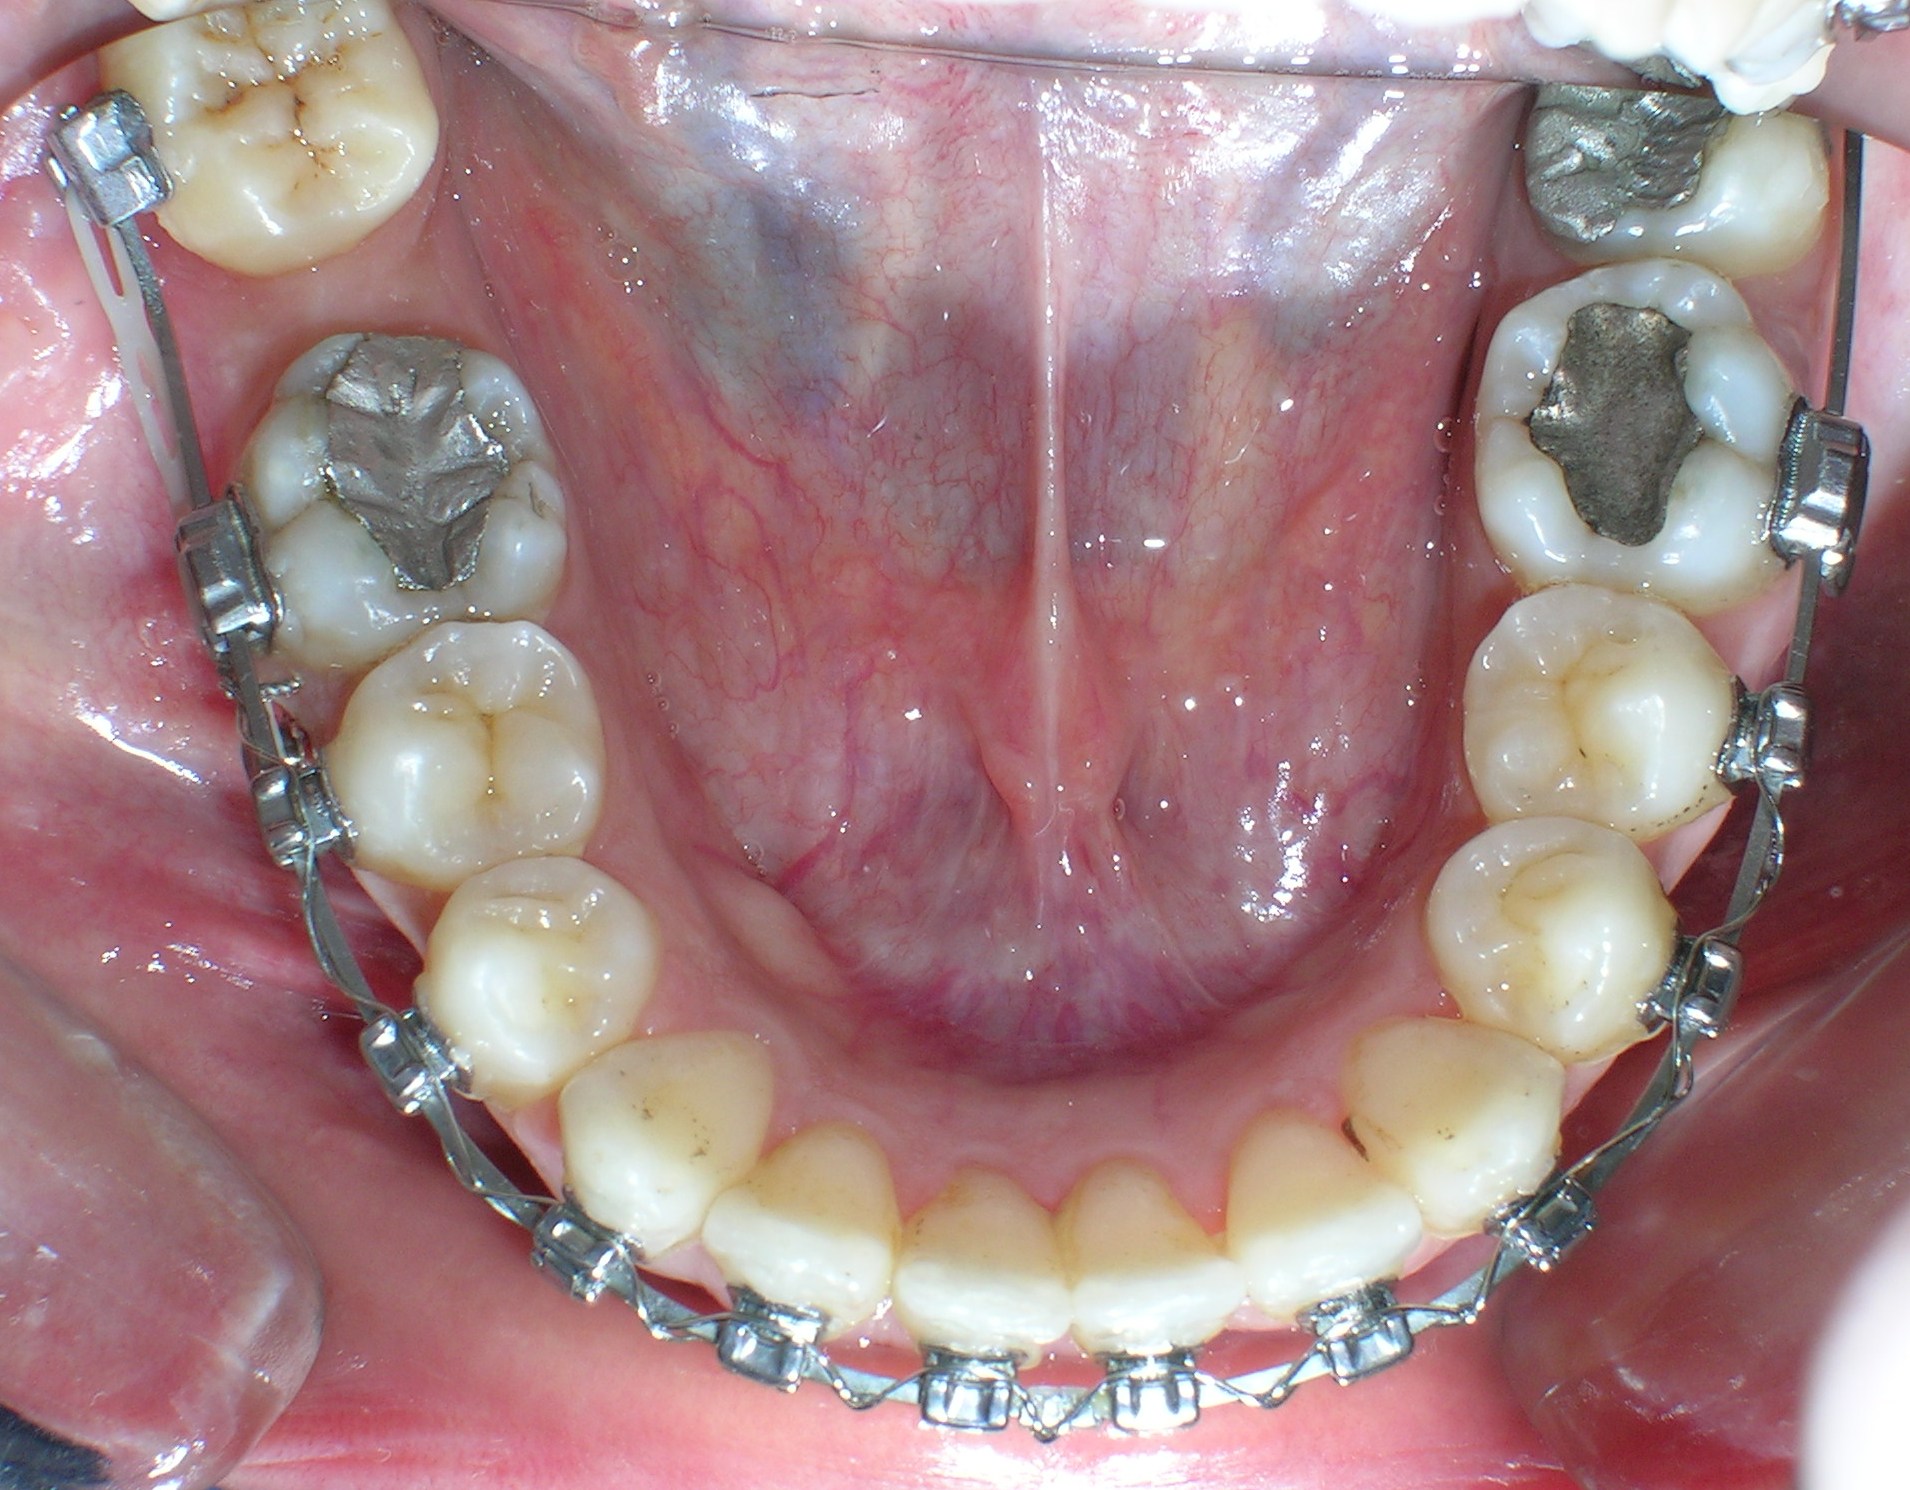

تعريف عام تقويم الأسنان هو فرع من طبِ الأسنان يَتخصّصُ في التشخيصِ ومنعِ ومعالجةِ الشذوذات والتغيرات في الأسنانِ والعظام الفكية الوجهية من حيث الموضع والحجم وعلاقة الأسنان والفكين ببعضها البعض. إنه يتعلق بتقويم الأسنان والفكين من أجل تحسين الابتسامة وصحة الفم. تعني كلمة "أورثو" أن الشيء سليم أو مستقيم في قوامه وتعني كلمة "أودونت" سنا. في العادة يوصي طبيب الأسنان بتركيب أجهزة تقويم الأسنان لتحسين المظهر الطبيعي لوجه وفم المريض. تَتطلّبُ ممارسةُ التقويم المعرفة المحترفة في وضع خطة العلاج وتطبيقِ الحاصرات السنية والتحكم بها لتحريك وجَلْب الأسنانِ والشفاهِ والفكين إلى الاصطفاف الصحيحِ والتوصّلُ إلى التوازنِ الوجهيِ. فمن خلال العلاج بتقويم الأسنان يتم معالجة المشاكل الناتجة عن الأسنان المتعوجة أو المتزاحمة وبروز الفك العلوي أو العضة المفتوحة وسوء وضعية الفك واضطرابات مفاصل الفك. بعد أخذ الأشعة والصور اللازمة يقوم طبيب التقويم بالعلاج اللازم وذلك بتثبيت أسلاك من المعدن على الأسنان أو يركب له جهاز متحرك ، ويتطلب ذلك العديد من الزيارات للطبيب على فترات متباعدة يحددها الطبيب المعالج حسب حالة كل مريض ويجب على المريض الاهتمام بتفريش أسنانه خلال فترة العلاج كي يتلافى ألإصابة بتسوس الأسنان أو ألتهاث اللثة نتيجة تراكم طبقة البلاك على أسنانه وأسلاك التقويم. التقويم يُمْكِنُ أَنْ يَرْفعَ ثقة الشخص بشكله ومظهره الشخصي عندما تصبح الأسنان والفكين والشفاه بوضعها الصحيح، لكن الابتسامةَ الجذّابةَ هي فقط إحدى فوائد التقويم الذي يؤدي أيضا لتَخفيف أَو مَنْع المشاكلِ الصحية بشكل عام، وهذا ما يعطي التقويم أهمية خاصة. فقط للحصول على ابتسامة رائعة و لكن صحّية أيضاً. الأسنان الموزعة باستقامة صحيحة في الفم تُحسّنُ إلى حد كبير الناحية الوظيفية في المضغ والبلع والكلام وتجعل التنظيف أسهل وأكثر فعالية وفائدة. الابتسامة الجميلة شيء رائع سواء عند امتلاكه أو رؤيته. الابتسامة الجذابة هي البداية فقط لكن تحسن الصحة الفموية والعامة تظل من الأهدافَ الم.همة في المعالجة التقويمة. أجهزة تقويم الأسنان الأجهزة الثابتة عبارة عن وحدات تقويمية صغيرة تثبت على كل سن، حيث يمرر بداخلها سلك معدني لتتم عملية تحريك الأسنان وهناك أنواع للحاصرات وهى: معدنية ستاليس ستيل ذات لون فظي. خزفية شفافة مشابهة للون الأسنان. ذهبية معدنية مطليه باللون الذهبي. هذه الأنواع جميعها تؤدى نفس الفعالية في العلاج والاختلاف الوحيد فيها هو لونها وشكلها الخارجي فالحاصرات المعدنية هى النوع السائد في التقويم بينما الخزفية نادرا ما تستخدم لأنها أغلى من المعدنية و.تحتاج إلى رعاية أكثر لسهولة كسرها وهى مرغوبة من النساء أكثر لأنها شفافة فلا يظهر من التقويم سوى السلك المعدني. اهمية تقويم الاسنان التنفس الصحيح استخدام الأطفال للمصاصة بالطريقة الخاطئة لمدة طويلة قد يؤدي الى ضيق الفك العلوي مما يسبب تنفس الطفل من فمه بدلاُ من انفه وهذه المشكلة سوف تصحح تلقائياً عند توسيع الفك العلوي باستخدام التقويم. الكلام بشكل جيد سوف يواجه ألإنسان صعوبة في النطق الجيد وذلك بسبب عدم انطباق الأسنان بالشكل الصحيح. وعدم القدرة على النطق الصحيح قد يؤثر على نفسية ألإنسان. الشكل الجميل إذا كانت وضعية الأسنان غير صحيحة فهذا سوف يؤثر على طريقة الكلام فستجد البعض يضع يده أمام فمه والآخر يقفل شفتيه ليخفي أسنانه وهذا بدورة سوف يجعل الكلمات غير واضحة واعوجاج وتزاحم أسنان الأطفال قد يؤثر على مستواهم الدراسي وذلك لخجلهم من أسنانهم فتراهم لا يشاركون ولا يتجاوبون مع مدرسيهم مما يجعل المدرسين يأخذون فكرة وصورة غير جيدة عنهم كعدم الاهتمام. الحالات التي تحتاج الى علاج التقويم التزاحم الشديد بين الأسنان الأمامية أو الخلفية – وجود فراغات كبيرة بين الأسنان الأمامية – وجود عضة أمامية مفتوحة – وجود عضة أمامية عميقة بحيث تغطي الأسنان الأمامية العلوية الأسنان الأمامية السفلية تغطية كاملة أو قريبة من الكاملة – وجود عضة أمامية معكوسة – عدم أو سؤ تطابق الأسنان الخلفية – بروز الأسنان الأمامية |